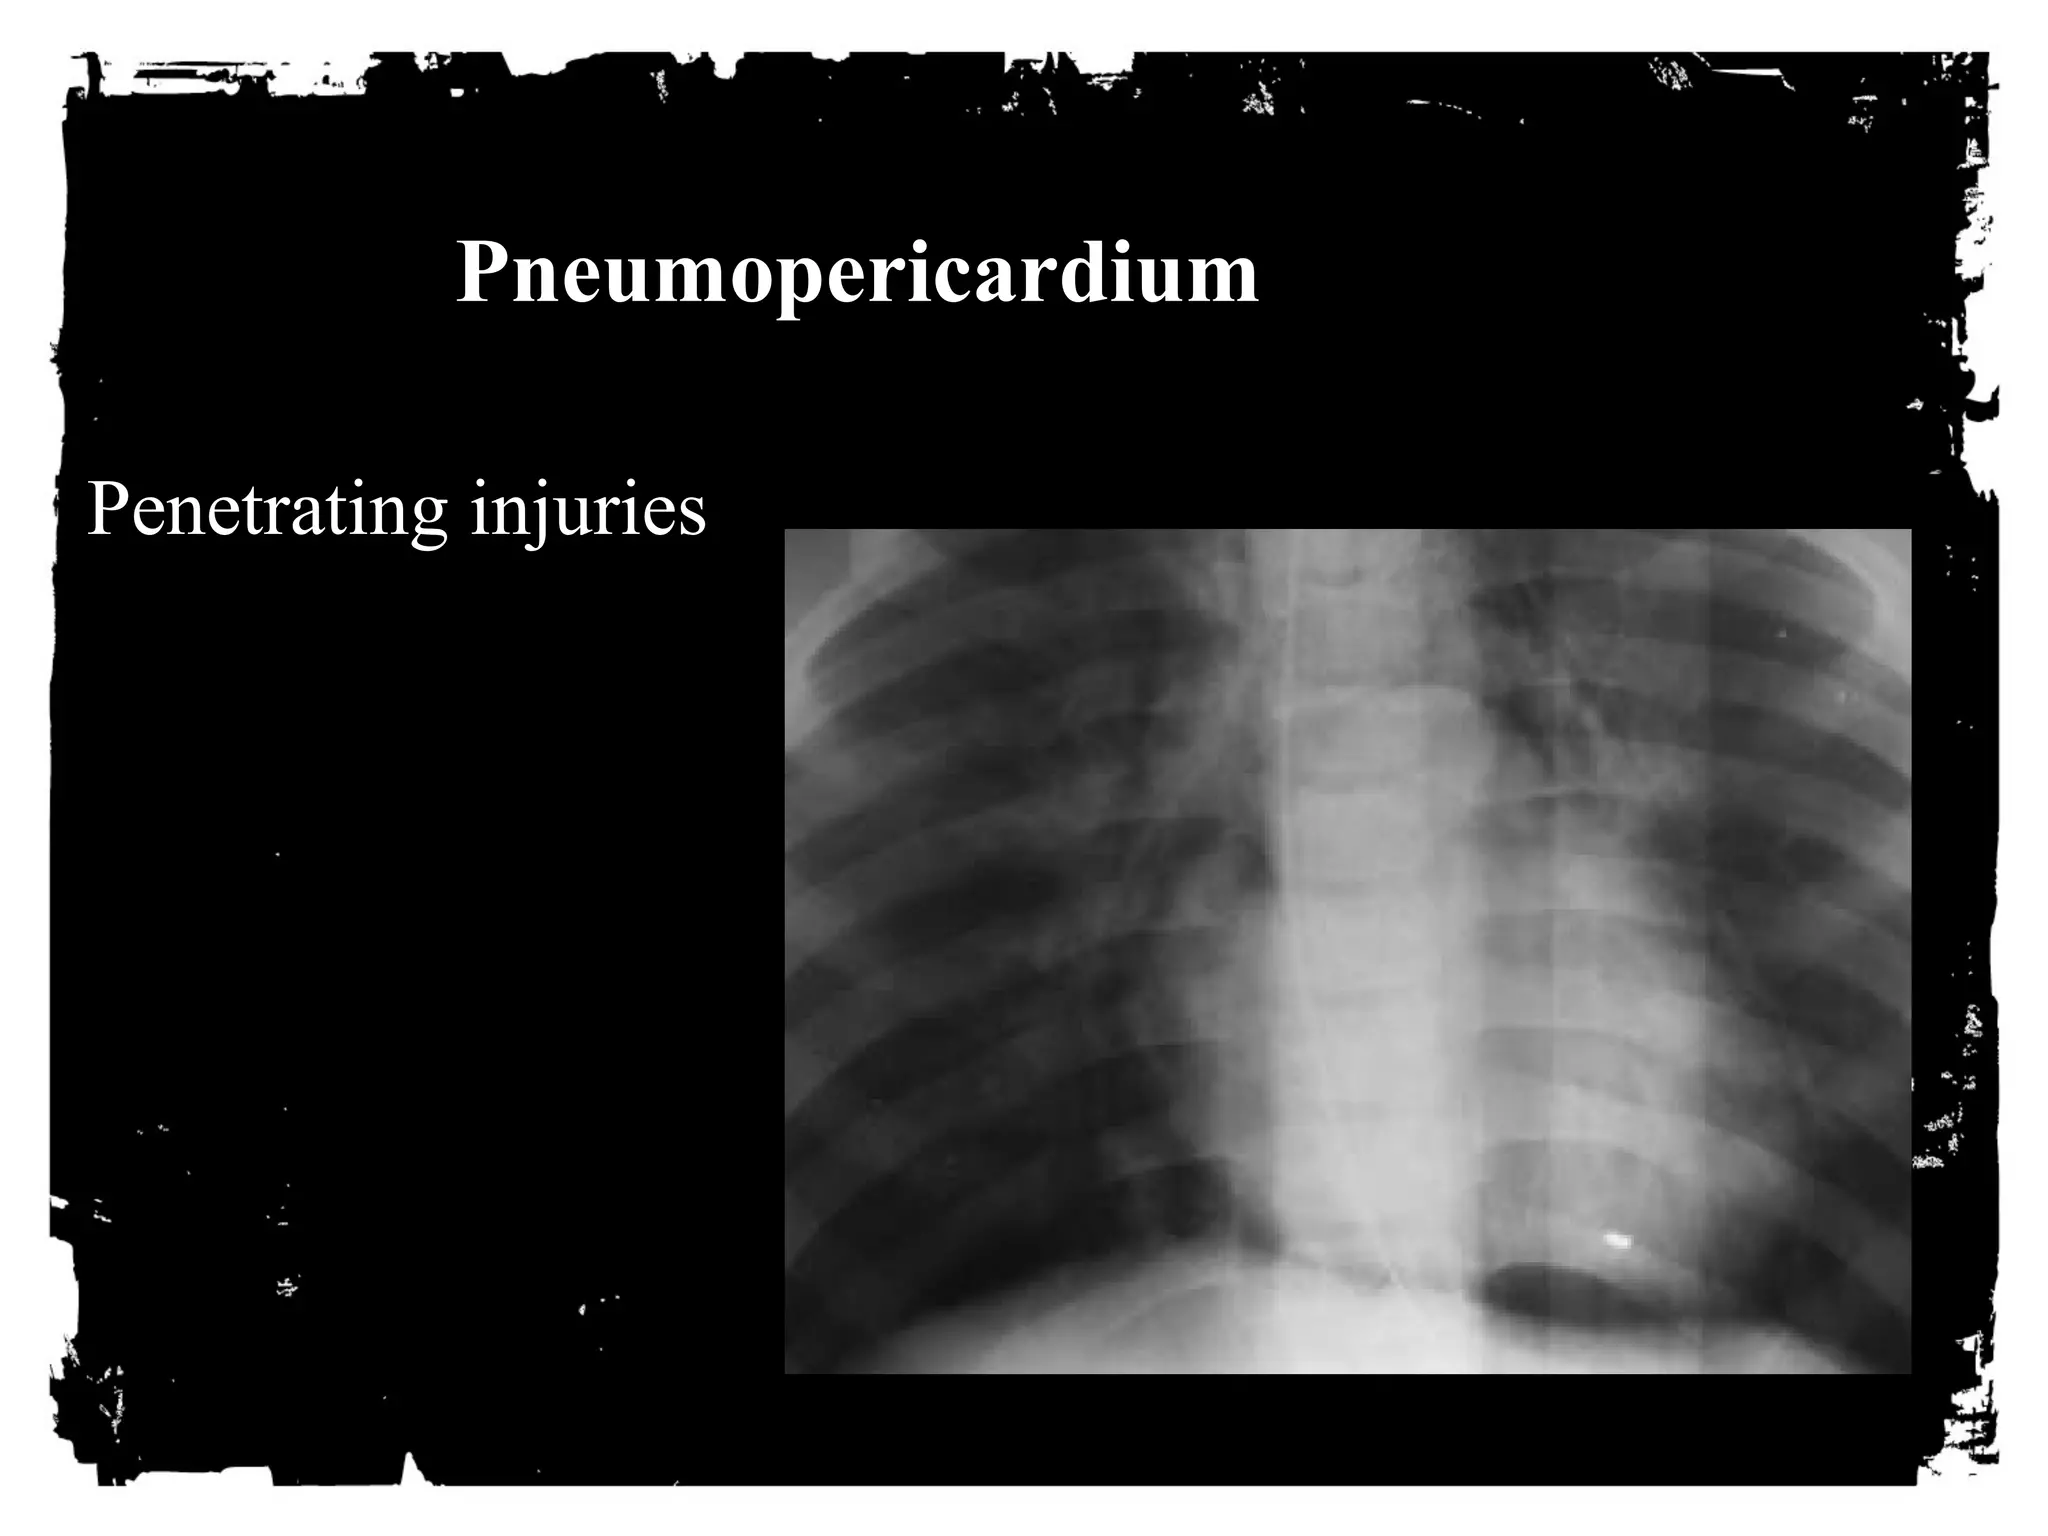

Pneumopericardium

Penetrating injuries